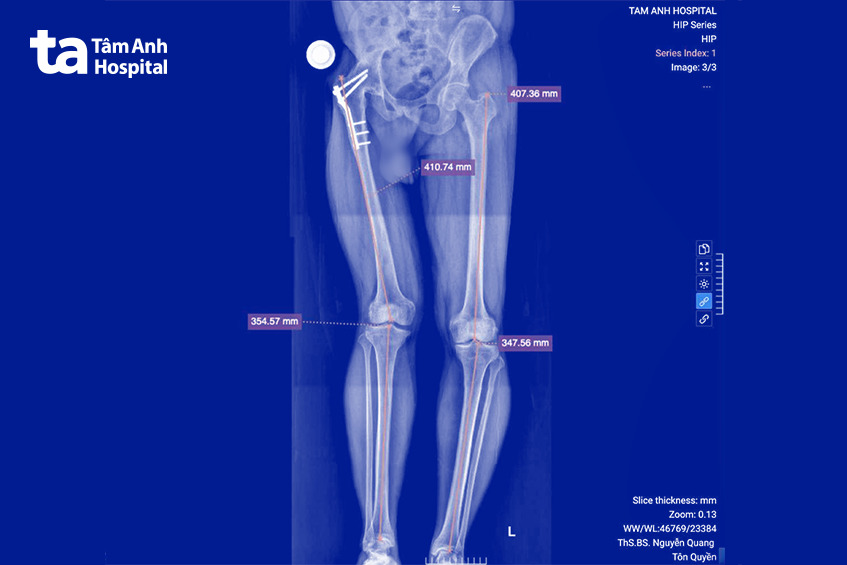

ThS.BS Nguyễn Quang Tôn Quyền, Phó trưởng khoa Chấn thương chỉnh hình cho biết ngay khi anh Giang bước vào phòng khám, bác sĩ đã cảm nhận đây là một trường hợp cực kỳ hóc búa, khớp háng đã bị đóng cứng hoàn toàn trong tư thế duỗi, sẹo mổ cũ chằng chịt và teo các cơ quanh vùng mông. X-quang cho thấy khớp háng đã đóng cứng, khung chậu và cột sống biến dạng nghiêm trọng, gây lệch chiều dài chi khoảng 3 cm.

Do đó, ngay từ trước mổ, ca phẫu thuật của anh Giang đã được lên kế hoạch rất tỉ mỉ. Bác sĩ Quyền sử dụng phần mềm chuyên dụng để đo đạc chi tiết cấu trúc xương của anh Giang, lên các phương án giải phóng khớp, tạo hình lại ổ cối và đặt khớp nhân tạo tại vị trí tối ưu, khôi phục tối đa chức năng vận động trong ngưỡng an toàn cho phép. Một trong những quyết định khó khăn nhất là phải tính toán để chọn cấu phần khớp nhân tạo phù hợp nhất với cấu trúc xương của bệnh nhân, đồng thời phải là loại khớp được bảo hiểm y tế chi trả để giảm bớt gánh nặng chi phí cho người bệnh.